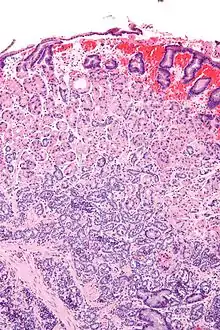

![]() صورة مجهرية لورم عصبي صماوي في المعدة. صبغة H&E. صورة مجهرية لورم عصبي صماوي في المعدة. صبغة H&E. | |